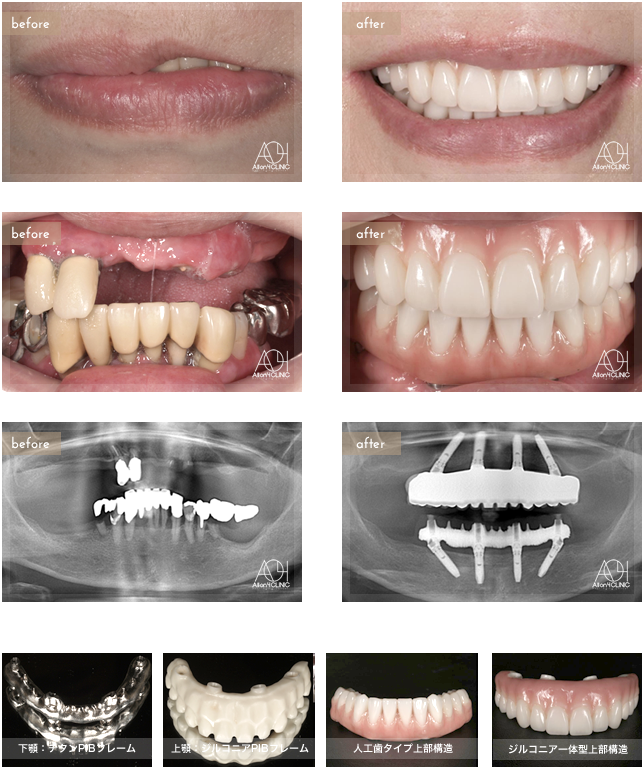

重度歯周病により、全顎的All-on-4による治療。上顎上部構造はジルコニア一体型(歯肉:セラミック/歯:セラミック/ジルコニアPIBフレームに歯肉・歯ともにセラミックを築成)を採用。下顎は人工歯タイプを採用。上顎はジルコニアPIBフレーム。下顎はチタンPIBフレーム。